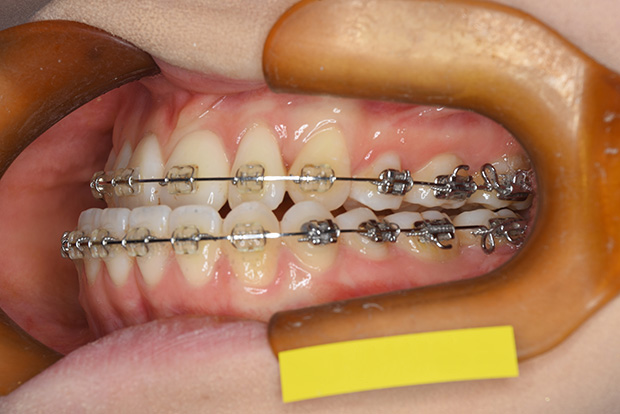

【叢生】抜歯 表側マルチブラケット装置

| 主訴 |

ガタガタ、上の歯が裏側に入っている |

||

|---|---|---|---|

| 診断名 |

左側側切歯crossbiteを伴うAngle I級上下顎前突 |

||

| 年齢 | 21歳 | 性別 | 女性 |

| 治療に用 いた装置 |

唇側マルチブラケット装置 (メタルワイヤー) | 抜歯部位 | 上下顎両側第一小臼歯 |

| 治療期間 ・回数 |

2年6か月・30回 | 治療費 概算 |

約75万円 (調整料を含む) |

| 治療内容 詳細 |

表側のマルチブラケット装置で治療した典型的な抜歯症例です。抜歯したスペースを利用して前歯を後退させ、ガタガタを解いています。 |

||

| リスク・ 副作用 |

装置による違和感。疼痛など |

||